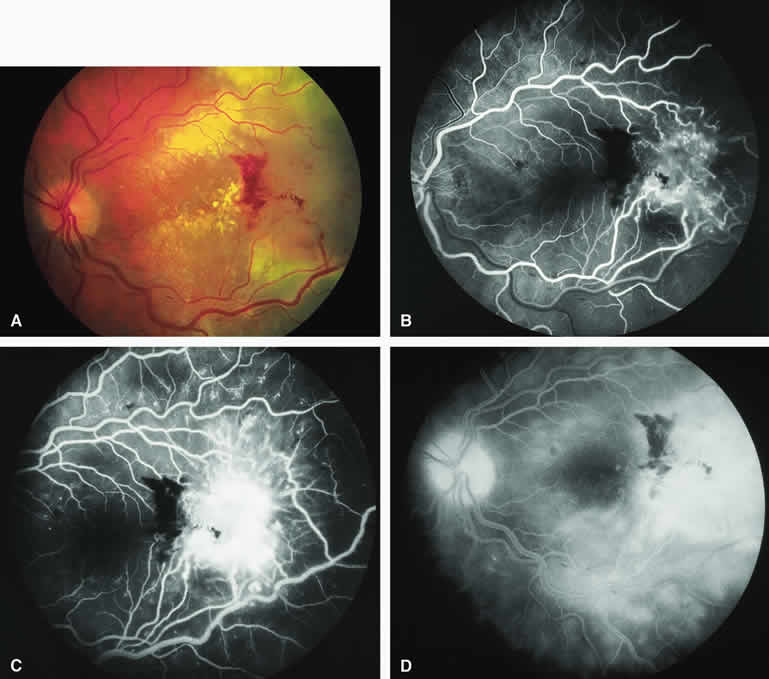

Choroidal Melanoma With Nodular Eruption Through Bruch's Membrane

If a choroidal melanoma has erupted through Bruch's membrane (Figs. 13A and 14A), it forms an apical nodule that is generally hypomelanotic and contains many large-caliber blood vessels. Fluorescein angiography of these tumors (see Fig. 13B, C, and D) typically shows hypofluorescence of the base of the lesion during the early frames, relatively rapid filling of the prominent blood vessels in the apical nodule during the venous and recirculation frames, and intense late staining of the apical nodule resulting from progressive fluorescein leakage by the late-phase frames. Similarly, ICG angiography of these tumors (see Fig. 14B, C, and D) also shows relative early hypofluorescence of the tumor base, early filling of prominent intralesional blood vessels within the apical nodule, intense staining of the apical nodule by the recirculation phase frames, and persistent late hyperfluorescence of the mass.